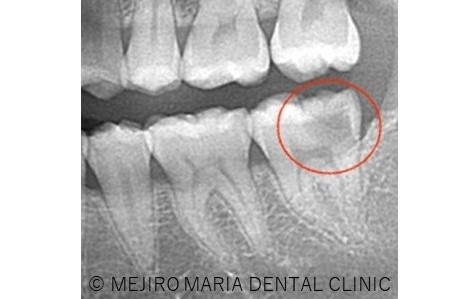

診査の結果、虫歯の進行はレントゲン上歯髄まで達していると思われましたが、厳密な歯髄診査の結果、診断は可逆性歯髄炎であり、生活歯髄保存療法が適応になると判断いたしました。

軟化象牙質(虫歯)を完全に除去した後に、歯髄を2mm程切断し、MTA(歯科用コンクリート)を充填しました。